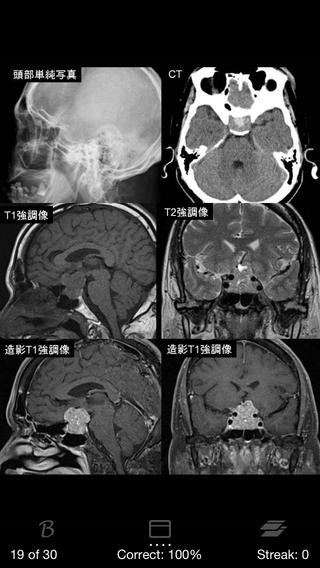

5.脳腫瘍日常臨床(1,400円)

引用元:https://itunes.apple.com/jp/app/id596370666?mt=8&ign-mpt=uo%3D4

レジデントの先生方、専門医の先生方を対象としたアプリです。

代表的な脳腫瘍30疾患に対するQ&Aと参照用データが、

全9章、180ページにわたって収録されています。